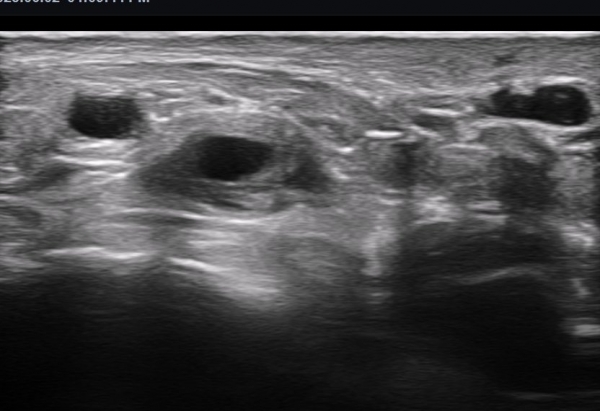

ÃÊÀ½ÆÄ ¼Ò°ß : ºñº¹½Å°æ Ⱦ´Ü¸é°Ë»ç¿¡¼­(»çÁø 1~13) ºñº¹½Å°æÀÇ Àú¿¡ÄÚ ºÎÁ¾°ú ´Üºñ°ñ°Ç³» ³¶Á¾¼º º´º¯ÀÌ °üÂûµÈ´Ù.

ºñº¹½Å°æ Á¾´Ü¸é°Ë»ç(»çÁø 14, 15)¿¡¼­ ºñº¹½Å°æÀÇ Àü¹ÝÀûÀÎ Àú¿¡ÄÚ ºÎÁ¾°ú ºñº¹½Å°æ ½ÉÃþÀ¸·Î ´Üºñ°ñ°Ç³»

³¶Á¾¼º º¯º¯ÀÌ °üÂûµÈ´Ù.